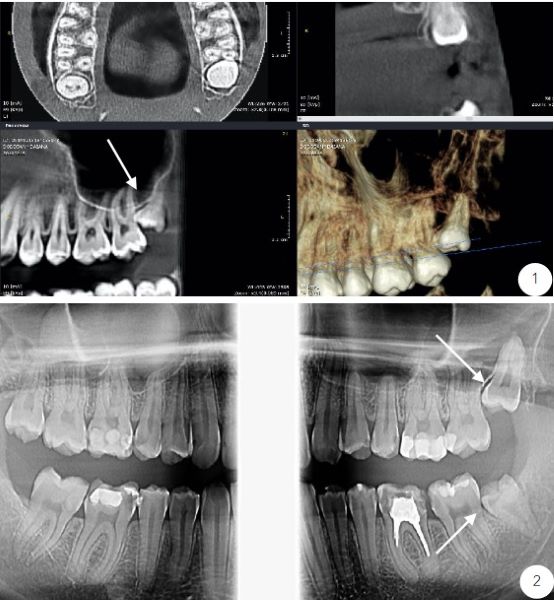

Exemple molari de minte incluși:

1. Extractie molar de minte superior stâng inclus, împinge în molarul 2 superior și creează resorbție ososă pe rădăcina distală a acestuia;

2. Molari de minte superiori și inferiori incluși care produc resorbție osoasă la nivelul rădăcinilor distale ale molarilor 2.